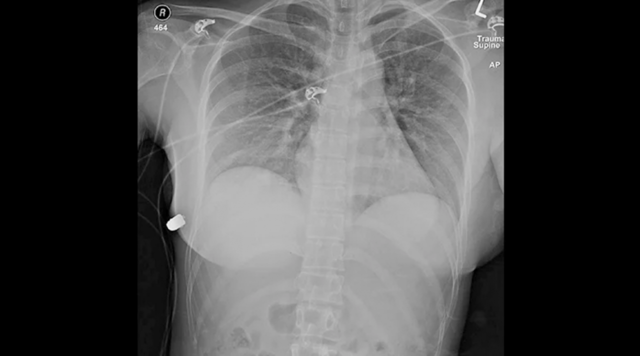

SAGE Journals dergisinde 15 Nisan'da yayımlanan makaleya göre; 2018 yılında 30'lu yaşlarında bir kadın Toronto'da sokakta yürürken birden göğsünde sıcaklık ve ağrı hissetti. Ardından mermi yarasını fark eden kadın hastanenin acil servisine başvurdu.

Doktorlar raporda, silikon üzerindeki izleri inceleyerek silikonun büyük bir ihtimalle kadının hayatını kurtardığı sonucuna vardı. Rapora göre vücuda sol taraftan vücuda giren mermi, kalbe doğru ilerleyebilecekken silikon sayesinde yön değiştirdi.

İmplantlarını alınan kadının sadece bir kaburgasında çatlak olduğu, onun haricinde durumunun iyi olduğu kaydedildi. Doktorlar, kadına yeni bir estetik ameliyatı yapmadan önce 6 ay beklemesini tavsiye etti.